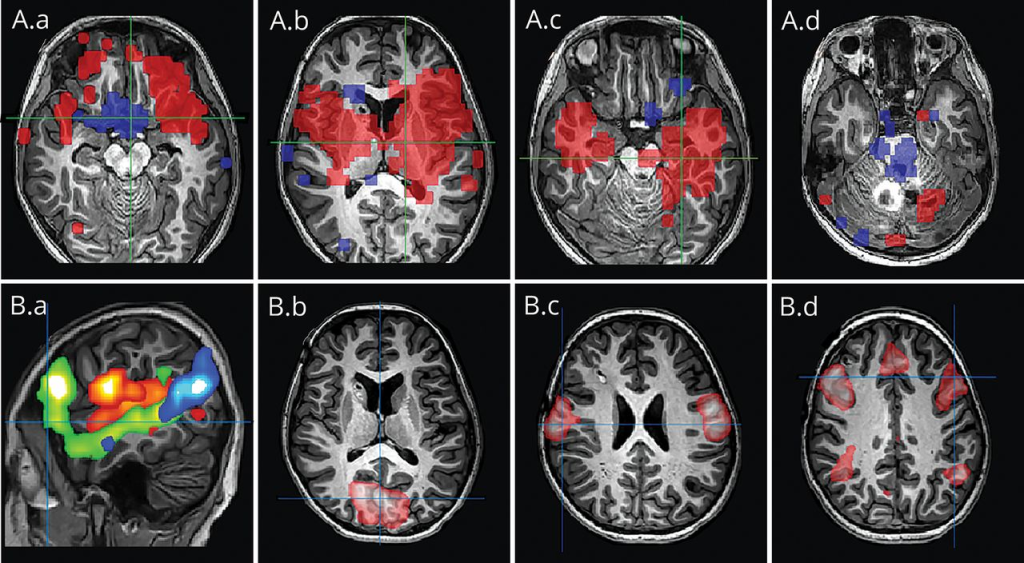

Since its inception, fMRI has dominated brain mapping research due to its noninvasive nature, eliminating the need for injections, surgery, substance ingestion, or exposure to ionizing radiation. Statistical procedures are employed to extract the underlying signal from potential noise sources, enabling graphical representation of brain activation by color-coding the strength of activation across the brain or specific regions. While it achieves remarkable localization within millimeters, temporal precision typically ranges within a few seconds².